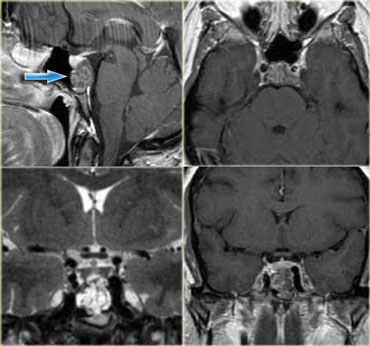

Melanoma metastasis: T2WI and T1WI Melanoma metastasis: T2WI and T1WI

Intra- vs Extra-axial (2)

The differentiation between intra-axial versus extra-axial is usually straight forward, but sometimes it can be very difficult and imaging in multiple planes may be necessary.

The tumor in the case on the left was thought to be a falcine meningioma, i.e. extra-axial and was presented for surgery.

This lesion surely has the appearance of a meningioma: these tumors can be hypointense on T2 due to a fibrocollageneous matrix or calcifications and frequently produce reactive edema in the adjacent white matter of the brain.

However, there is gray matter on the anteromedial and posteromedial side of the lesion (red arrow).

This indicates that the lesion is intra-axial.

If the lesion was extra-axial the gray matter should have been pushed away.

This proved to be a melanoma metastasis.